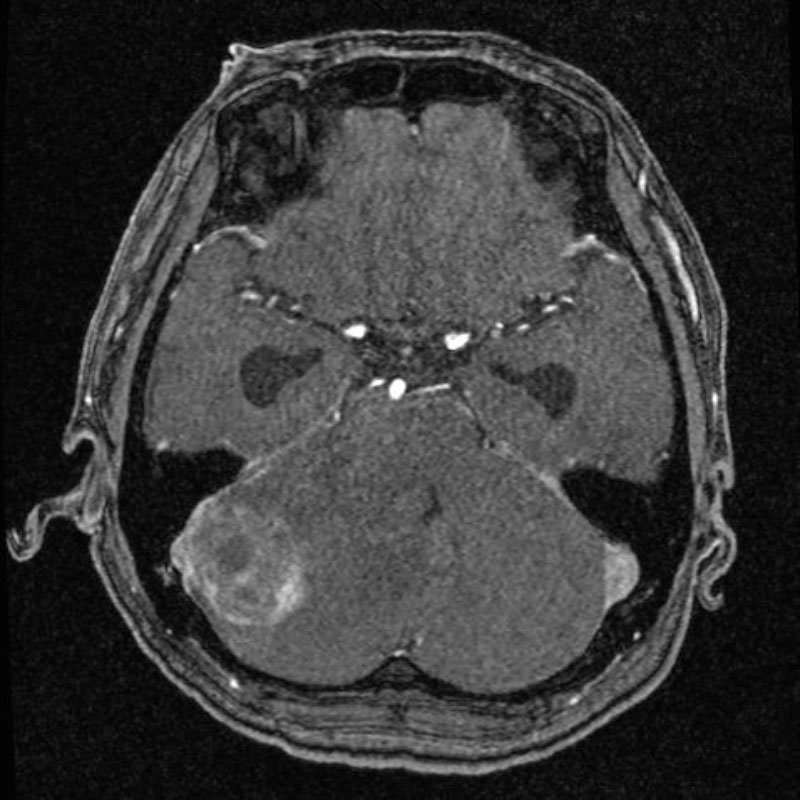

703

'25年12月

50代

先端巨大症

頭蓋内腫瘍摘出術

No.’25_105 手術前1

No.’25_105 手術前2